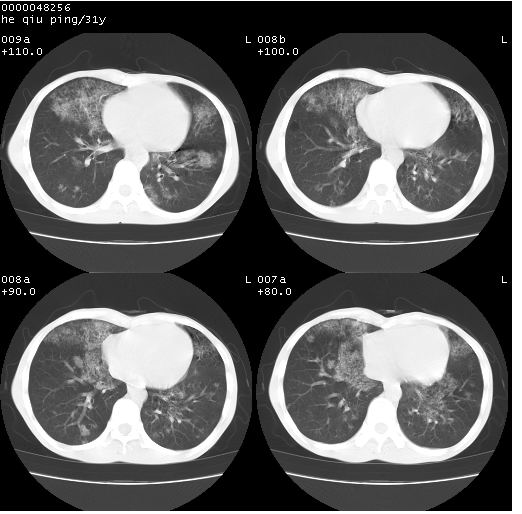

标题: CT13402:M,31Y。肺结核伴空洞形成? [打印本页]

标题: CT13402:M,31Y。肺结核伴空洞形成?

咳嗽半月余,消瘦体质,呼吸音弱。无其他病史。cr:肺转移瘤待。

双上肺多发空洞,双飞散在分布大小不一的片状结高密度影节状大片状高密度影。符合结合肉芽肿形成及空洞形成。

双侧弥漫性病变,双上叶尖后段、下叶北段见多个空洞,多见于结核感染。右中叶及双下叶斑片状,结节状影,考虑为肉芽肿形成及支气管播散。但由于患者消瘦体质,抵抗力低下,若继发感染,如金葡菌肺炎也有可能。

应该是比较典型肺结核伴空洞形成,下肺野播散。

考虑为:两肺结核伴多发空洞形成、支气管播散。

病灶多形性,有空洞形成。考虑肺结核伴空洞形成,两下肺支气管播散!